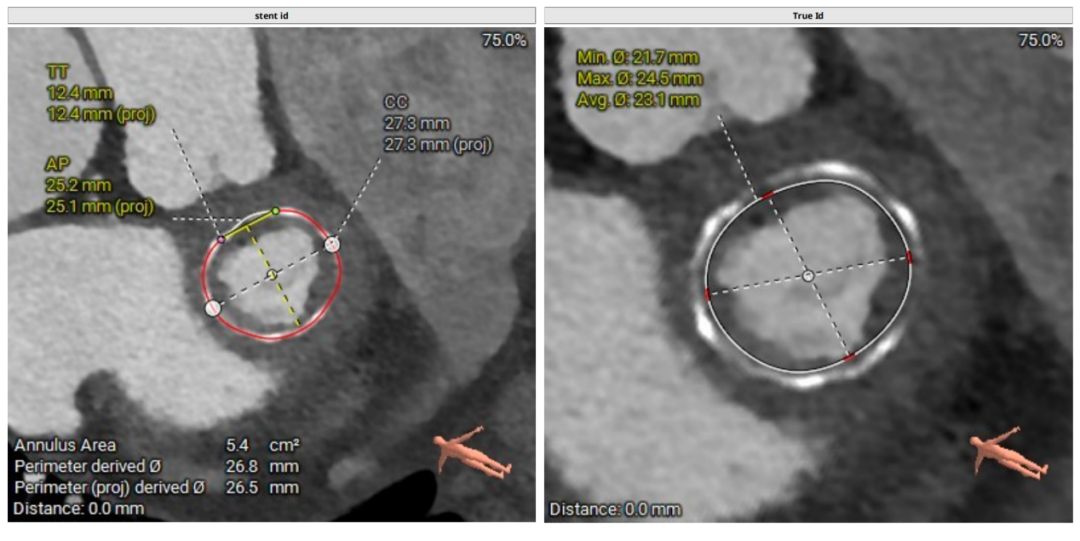

术前CT评估

二尖瓣生物瓣支架内径 26.5mm,结合瓣架形态、瓣架高度及手术记录,符合EPIC 27#。瓣中瓣治疗考虑选择25# 介入瓣膜。模拟25# 瓣膜植入,测得NEO-LVOT 面积155.8mm²,术后存在新流出道梗阻风险。左心耳尖端未见血栓。左心房增大73.4*118.7mm,房间隔未见增厚,未见明显钙化,靠后靠下房间隔穿刺点距二尖瓣水平高度27.7mm,房间隔穿刺点高度可。